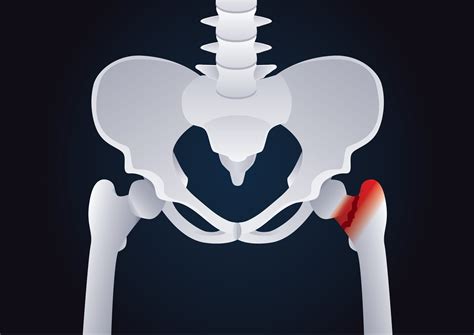

A hip stress fracture is a serious injury that occurs when repetitive stress or overuse creates tiny cracks in the bone, most commonly in the femoral neck. Unlike acute fractures caused by sudden impact or falls, a stress fracture develops gradually over time as the bone's ability to repair itself is overwhelmed by continuous mechanical loading. Often seen in long-distance runners, military recruits, and individuals starting intense new exercise regimens without adequate conditioning, this condition requires immediate attention to prevent severe complications. Recognizing the early symptoms and seeking prompt medical evaluation is essential to ensuring proper healing and avoiding long-term hip joint damage.

The hallmark of a hip stress fracture is pain that worsens with physical activity and subsides with rest. In the early stages, the discomfort may be subtle, often masked by normal muscle soreness. However, as the damage progresses, the pain becomes more localized and persistent.